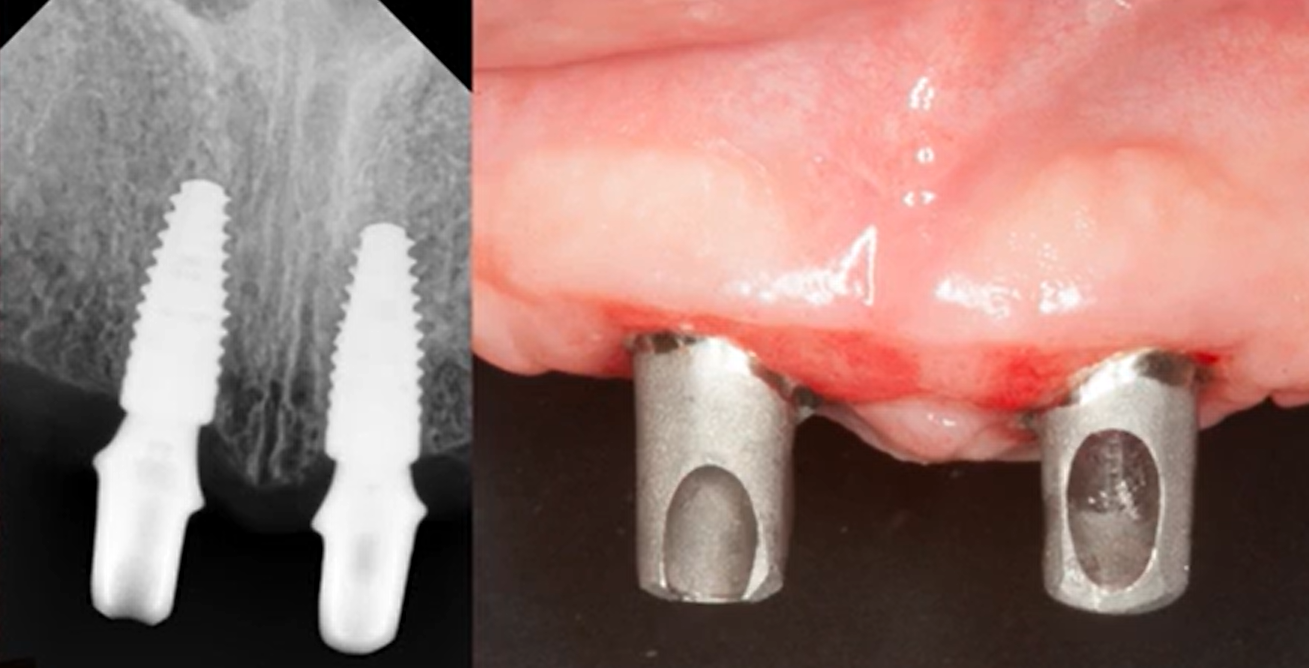

Now let’s look at another case and see what happens when Bone Level implants are used. Note the amount of attached gingival tissue in the completely edentulous jaw. The gingival tissue is thick and massive, which is a good sign.

Initial condition of the jaw with complete edentia, visual assessment: wide alveolar ridge, thick attached keratinized gingiva. YouTube/ Implantology/ Rauf Aliyev

So, at first glance, this patient’s outlook appears excellent. But during the surgery, this is what we see:

During the operation, it was discovered that the thickness of the soft tissue above the ridge ranged from 1.5 to 2 mm in different areas. YouTube/ Implantarium/ Rauf Aliyev

If you look at the palatal portion of the flap, you’ll see that it’s quite thin—about 2 mm or even slightly less. On the vestibular side, the flap is even thinner, about 1.5 mm.It turns out that at the initial examination, we see a wide alveolar ridge and a thick layer of attached gingiva—all of which is fine—but the soft tissue layer is vertically thin. This means that bone loss is inevitable.

The next photo is from the abutment try-in stage. From the frontal view, a strong band of attached gingiva is visible, which is excellent. This means the soft tissue connection will be stable and protected from mechanical stress during chewing.

And from this angle, we see that the alveolar ridge is wide and there is sufficient bone reserve on both the palatal and vestibular sides. And this is also very good.

But if you compare three x-rays:

- Immediately after implantation

- In 3 months

- After 12 months…you can see changes in the level of the marginal bone.

…you can see changes in the level of the marginal bone.

X-rays: immediately after implantation, 3 months and 12 months after implantation. YouTube/ Implantarium/ Rauf Aliyev

In summary, this “pure experiment” case demonstrates that the initial gingival thickness is the decisive factor for bone remodeling. Despite other positive factors such as:

- Broad alveolar ridge

- Good volume of keratinized attached gingiva

- Double platform switchingThe outlook for this restoration is still good, the formation of the gingival junction is complete, and the remaining bone contact is sufficient for implant stability, as the risk of gingival recession is minimal. However, if the patient has other negative factors, a loss of 1-2 mm of marginal bone can be critical for implant survival.